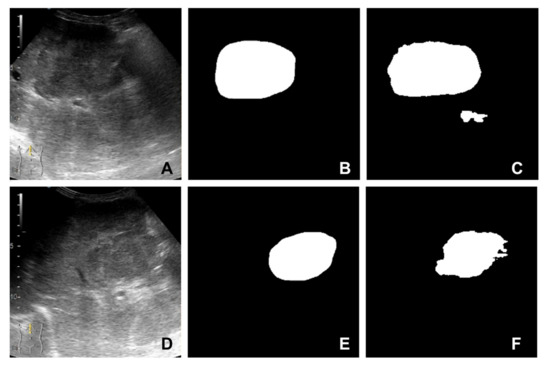

The U-Net [11] image segmentation model obtained from our previous work [10] was used to obtain region of interest for each frame in the video investigation file. By passing a frame from the ultrasound video investigation through the presented image segmentation model, a mask of 256 by 256 pixels is obtained. This mask can be further used to isolate the lesion from parenchyma in that specific video frame. Running a video investigation through the image segmentation model, the lesion is automatically isolated from the parenchyma, frame-by-frame, in the entire file; therefore, a time-intensity curve can be extracted from the investigation. A sample of inputs and outputs of the U-Net segmentation model are presented in Figure 2A–F.

Figure 2. Samples extracted from the image segmentation dataset: (A,D) B-mode frame cropped from the video investigation; (B,E) mask (label) created by the senior gastroenterologist; (C,F) the mask predicted by the segmentation model.